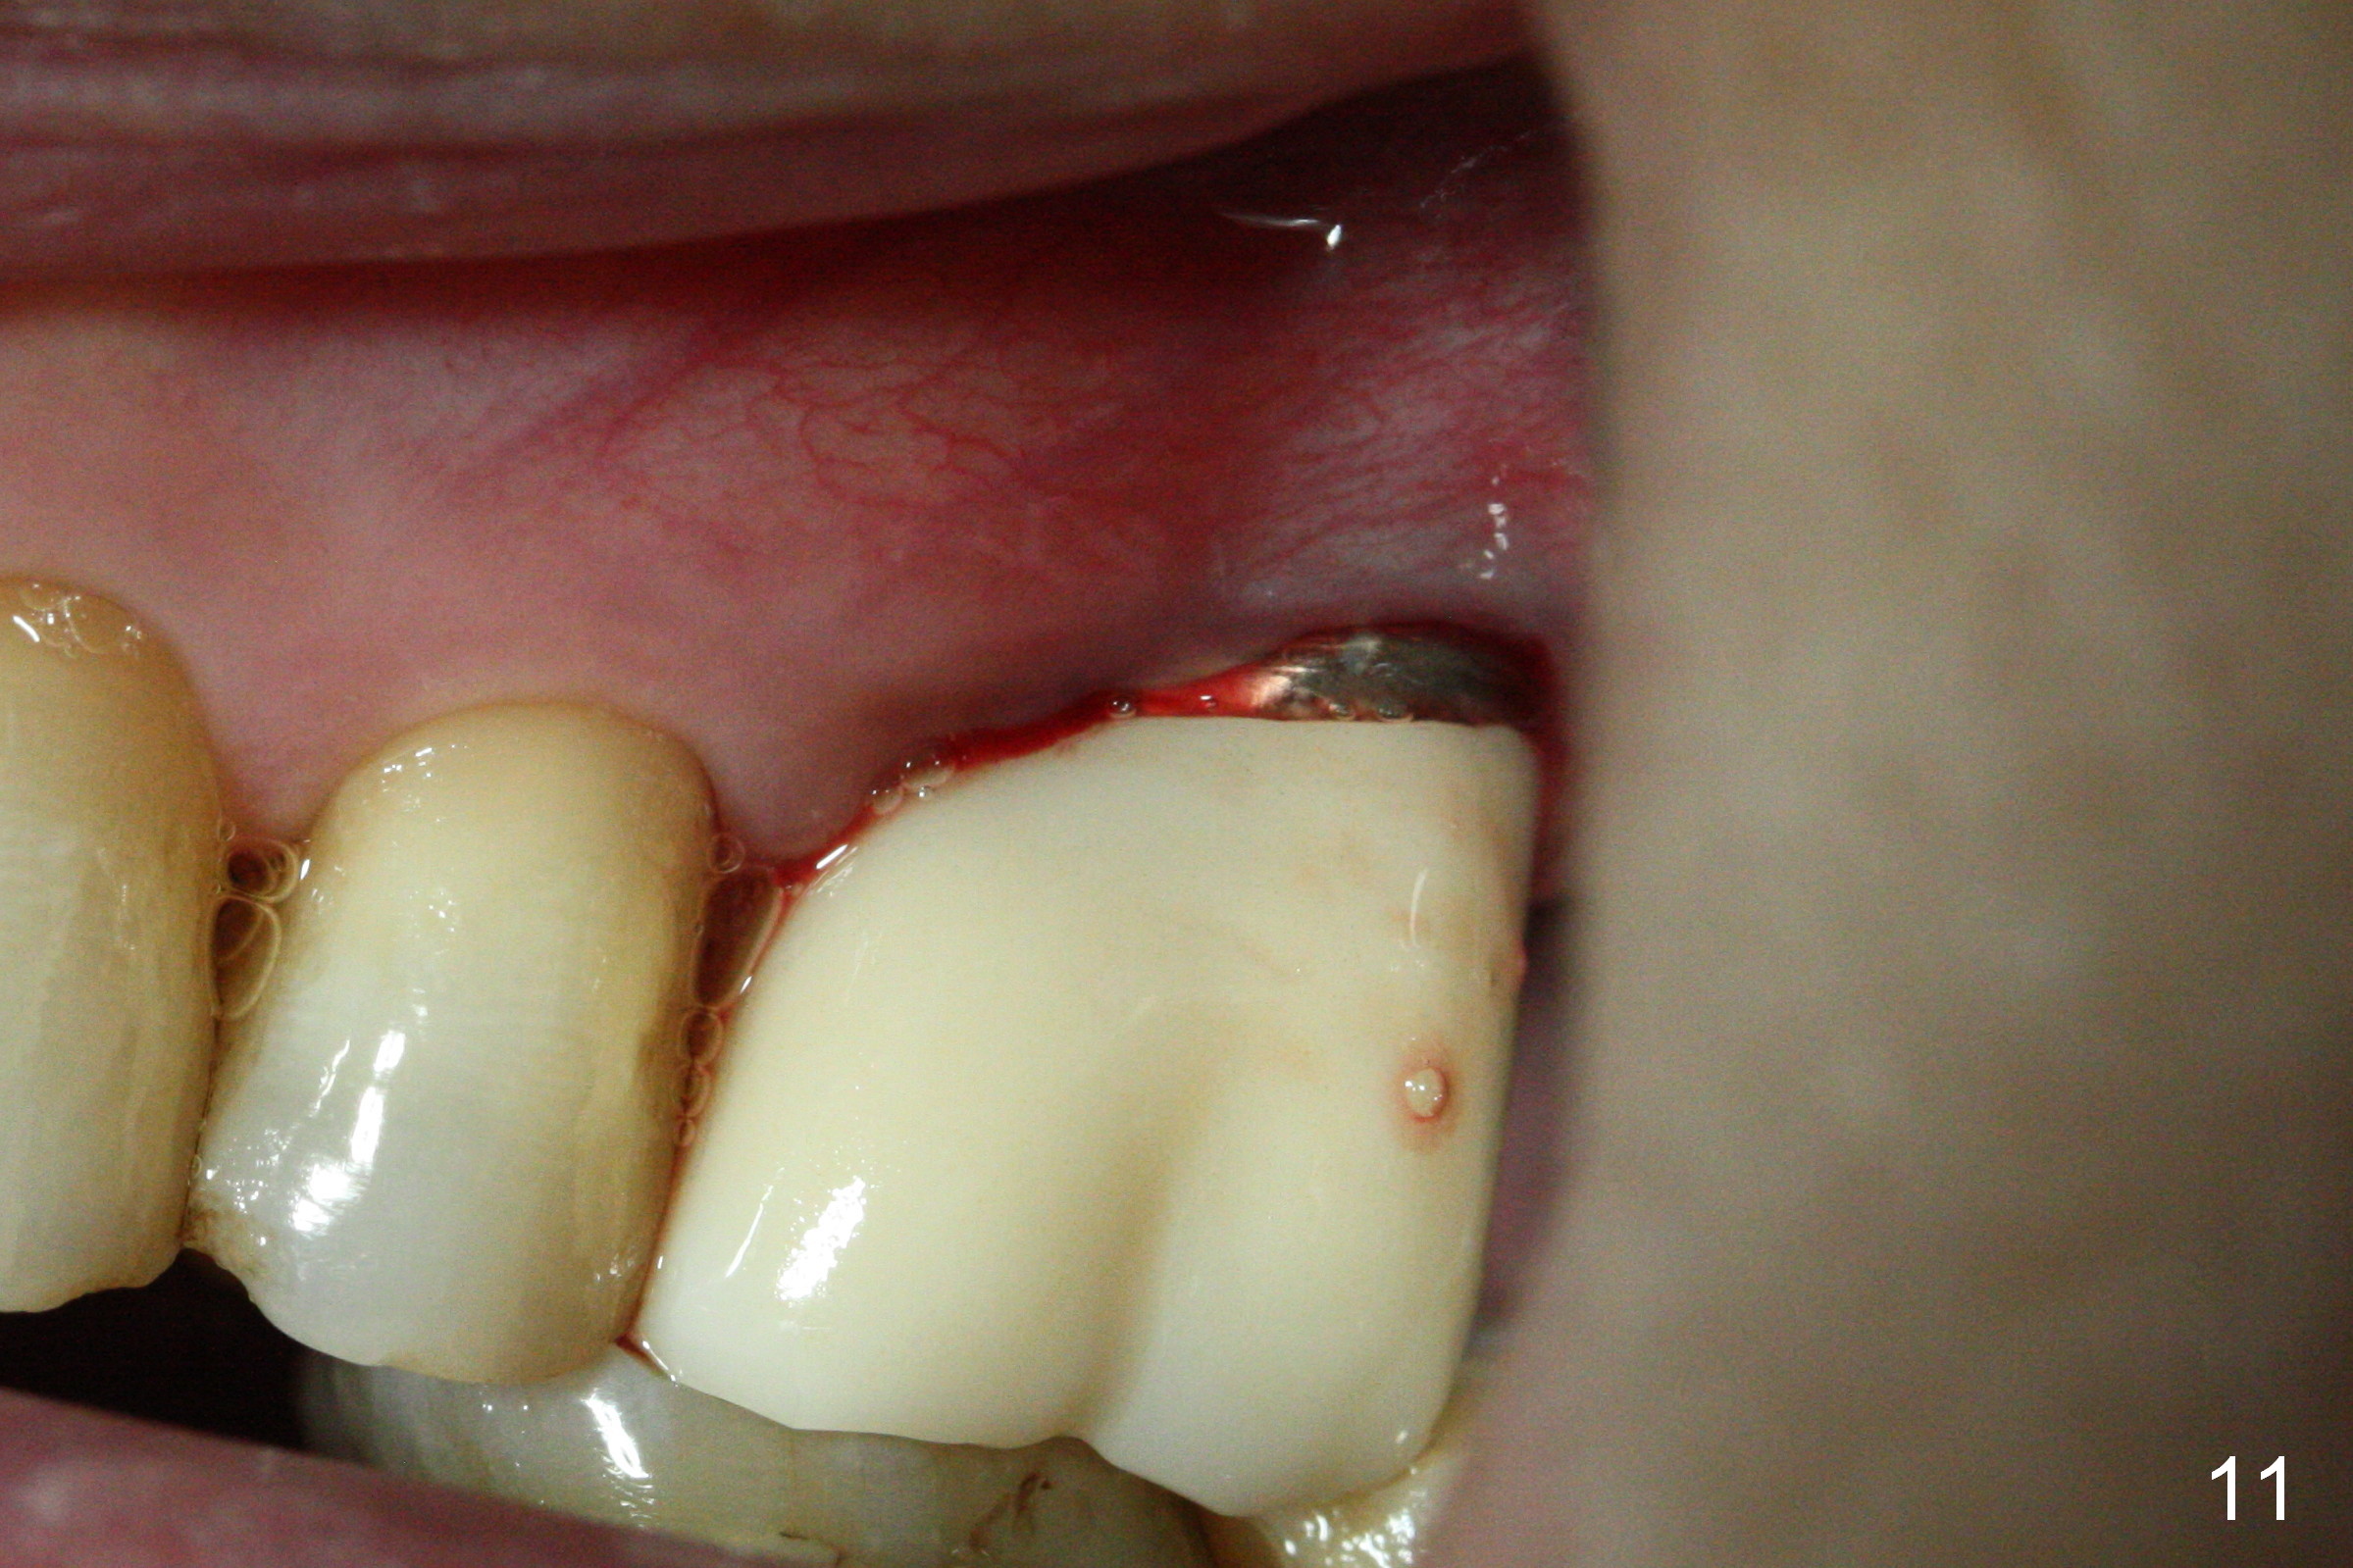

Crown is cemented 5.5 months postop.(Fig.9) and has been in function for more than 34 months (Fig.10,11).